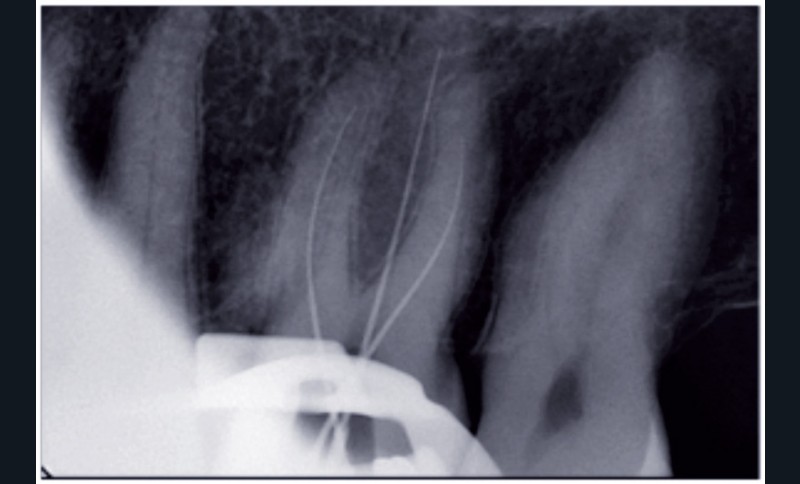

• Deux radiographies rétroalvéolaires sont effectuées

au cours du traitement endodontique : l’acte a pour code HBQK040 et pour libellé « Radiographies intrabuccales rétroalvéolaires sur un secteur de 1 à 3 dents contiguës préinterventionnelle ou perinterventionnelle avec radiographie finale pour acte thérapeutique endodontique ».

Les honoraires forfaitaires sont de 11,97 €.

• Trois radiographies rétroalvéolaires sont effectuées au cours du traitement endodontique : l’acte a pour code HBQK303 et pour libellé « Radiographies intrabuccales rétroalvéolaires sur un secteur de 1 à 3 dents contiguës préinterventionnelle, perinterventionnelle et finale pour acte thérapeutique endodontique ». Les honoraires forfaitaires sont de 15,96 €.

Dans les deux cas de figure, les dates des radiographies n’ont pas d’incidence sur le « tarif forfaitaire ». Ces radiographies peuvent être réalisées dans plusieurs séances (cas de la reprise du traitement endodontique, par exemple). Les honoraires restent ceux fixés forfaitairement.

Les données de la littérature professionnelle, tout comme la recommandation de la HAS (novembre 2008), conseillent de réaliser, au moins, trois radiographies pour un traitement endodontique. Même en utilisant un localisateur d’apex, la radiographie per-opératoire est essentielle pour doubler la mesure électronique par une mesure visuelle, broches en place.

Le « forfait deux radiographies » prévu par la CCAM est donc d’utilisation exceptionnelle.

La plupart du temps, l’acte d’endodontie est associé au « forfait trois radiographies ».